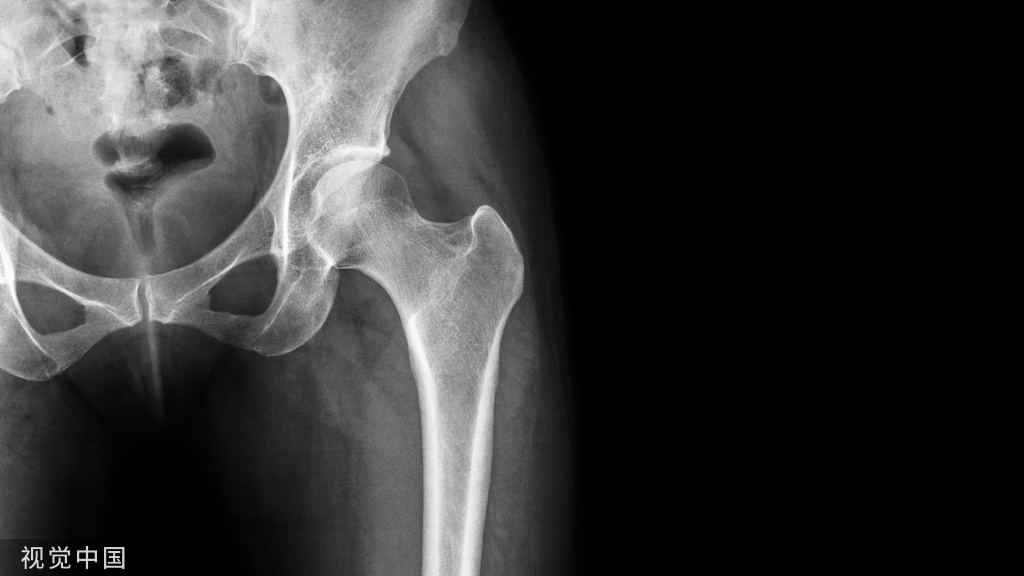

正常腰椎间盘表现

正常腰椎间盘后缘不超过椎体骨性终板的后缘,且中部略有凹陷呈肾形。